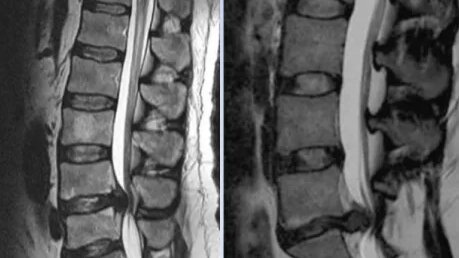

Задержка мочеиспускания, когда человеку трудно самостоятельно опорожнить мочевой пузырь, и запоры относятся к обширной группе расстройств органов малого таза. Причины таких тазовых дисфункций весьма разнообразны. Если проведенное обследование не выявляет никаких изменений в самих этих органах, то вероятно, что проблема кроется в нарушениях в пояснично-крестцовом отделе позвоночника. Особенно серьезной является ситуация, когда запоры и задержка мочеиспускания сопровождаются отдающими в ноги болями в пояснице, а также двигательными и сенсорными нарушениями...